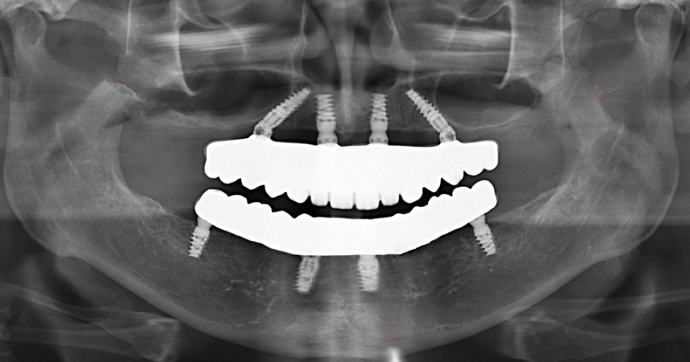

All-on-4/ Full Mouth Dental Implants / Teeth in a Day: Case 16-Upper and Lower All-on-4 Bridges

Patient had severe cavities throughout the mouth due to extreme dry mouth and history of use of tobacco. Patient was very discouraged as he had hated the idea of wearing dentures. Patient found Dr Bidra online and sought treatment and had all his teeth extracted and implants placed and new teeth installed all in 1 day! Patient was extremely satisfied with his transformation and eradication of all disease and bacterial infections.

Procedures : extractions, implants, All on 4 , Teeth in a day, no bone grafting and full mouth reconstruction with monolithic zirconia bridges.

Testimonial : "Dr.Bidra I cannot be thankful enough for the amazing treatment you have provided me so meticulously! I never thought this was possible but you made it happen. Thank you so much!